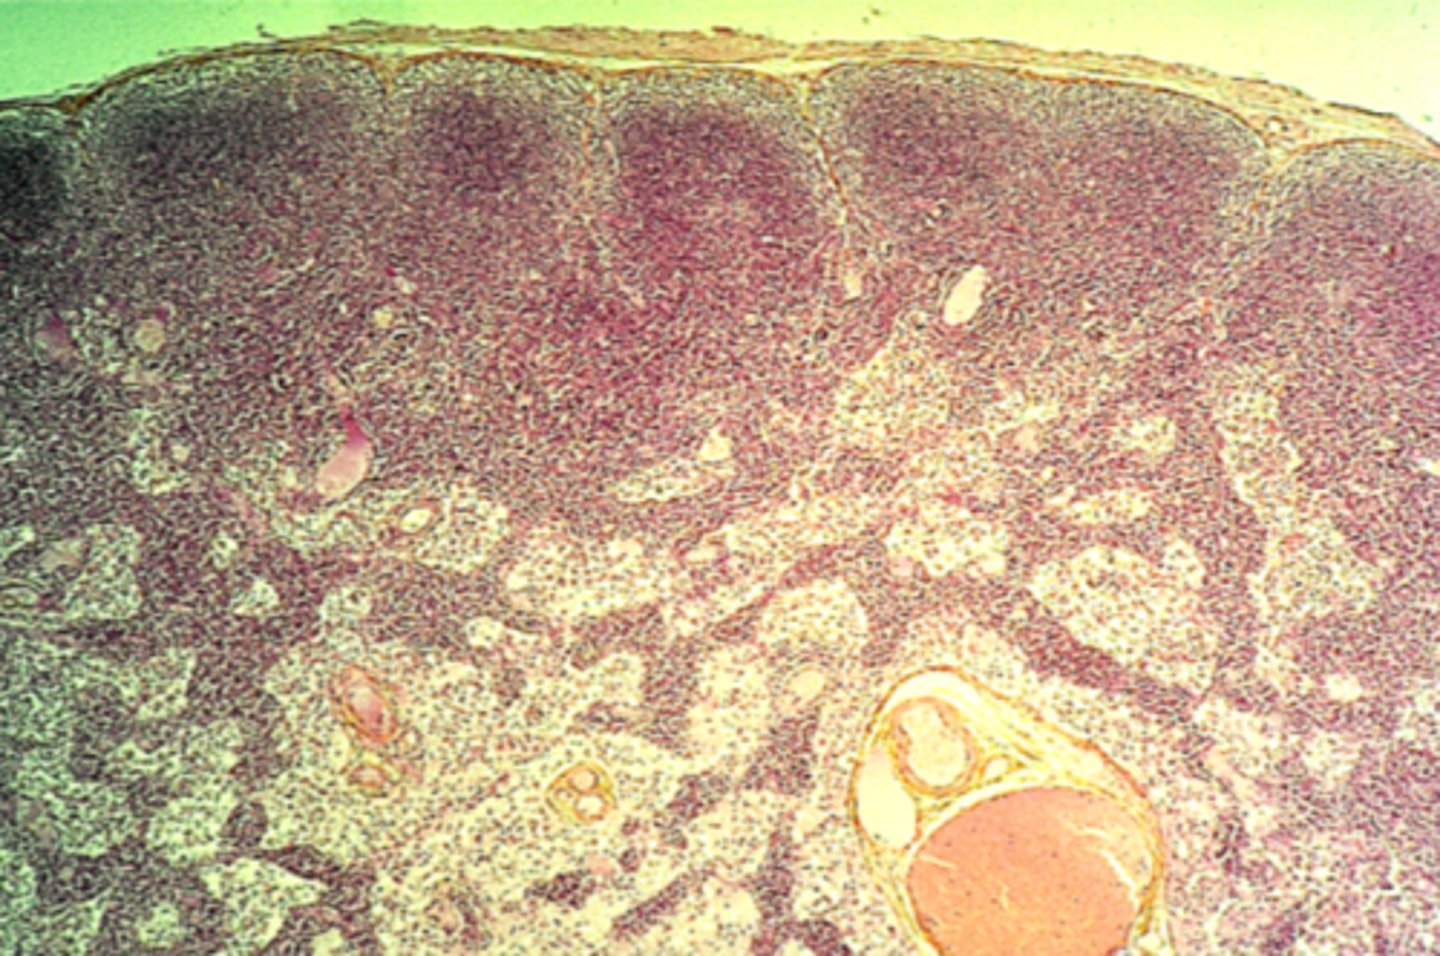

Lymph node

What is this?

Appendix

What is this?

Tonsil

What is this?

Thymus

What is this?